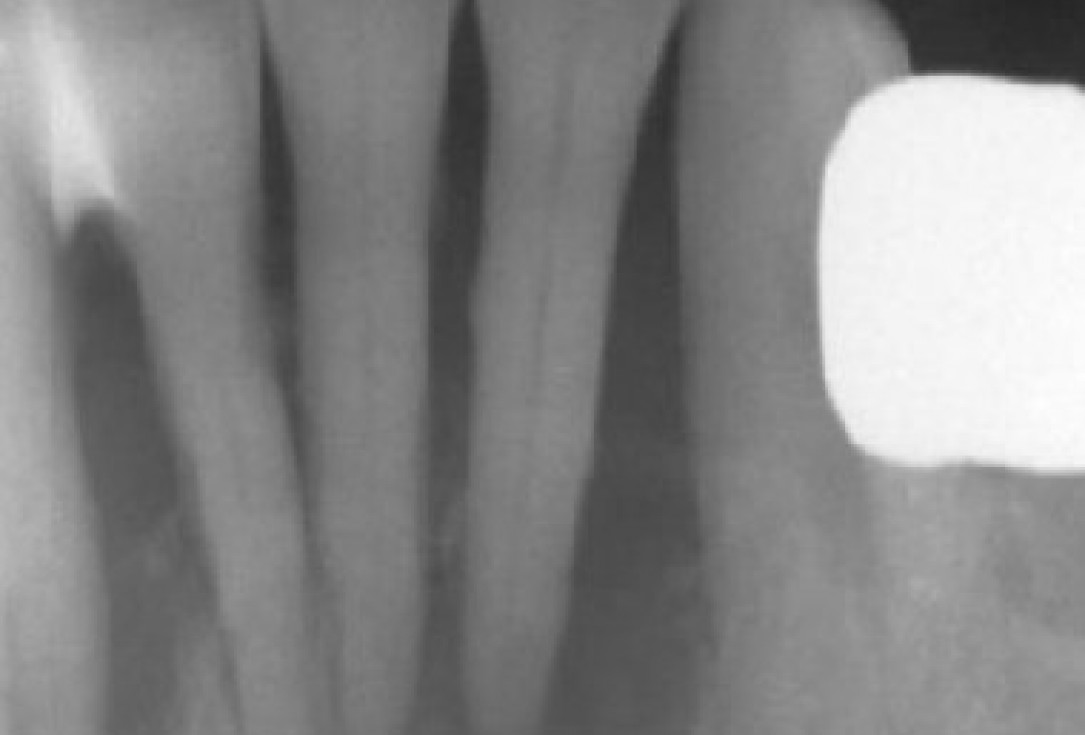

X-ray shows a 3-dimensional periondontal defect